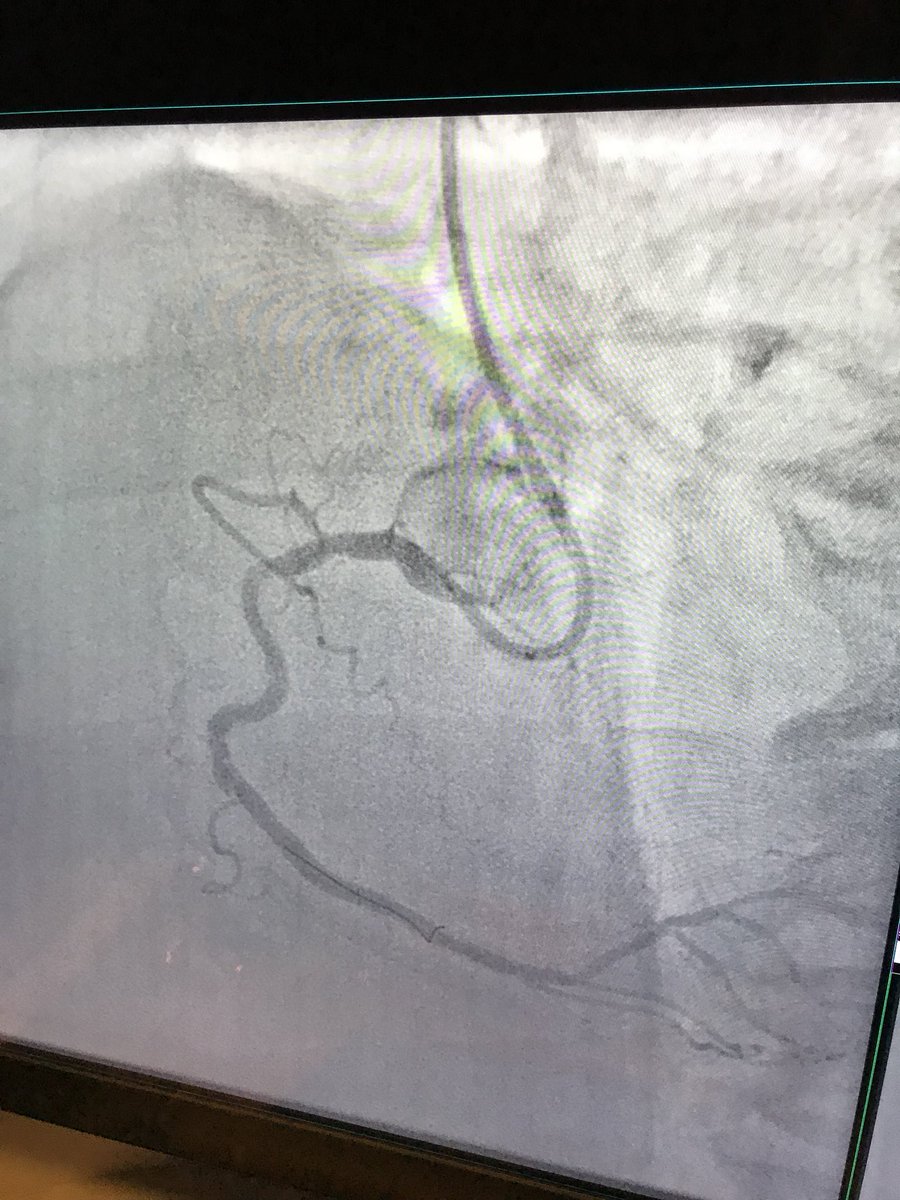

Robert W. Yeh Hector Tamez, MD MPH jcspratt Cut the distal dissection to provide outflow. This is 4.0 cutting balloon in d RCA

Robert W. Yeh Hector Tamez, MD MPH jcspratt Watch subintimal hematoma disappear as cutter deflates.

Robert W. Yeh Hector Tamez, MD MPH jcspratt Only stent the os. Dissection will heal.